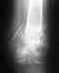

Уважаемые специалисты, 1 октября 26 летний мужчина, получил травму упав на параплане.Диагноз: перелом вертлужной впадины с вправленным подвывихом бедра. В суставной полости есть осколок 15 * 7 мм. В настоящее время проходит лечение на скелетной вытяжке (6 недель).Вопрос: есть ли необходимость в операции по извлечению осколка из суставной полости?

Диагноз представлен в несколько поверхностной форме. Переломы вертлужной впадины подразделяются на множество разновидностей, и показания к операции определяются далеко не только наличием свободных вргментов в суставе, что само по себе является показанием к операции. Однако задачи операции не ограничиваются лишь удалением свободных фрагментов, необходимо воссоздание конгруэнтной суставной поверхности.